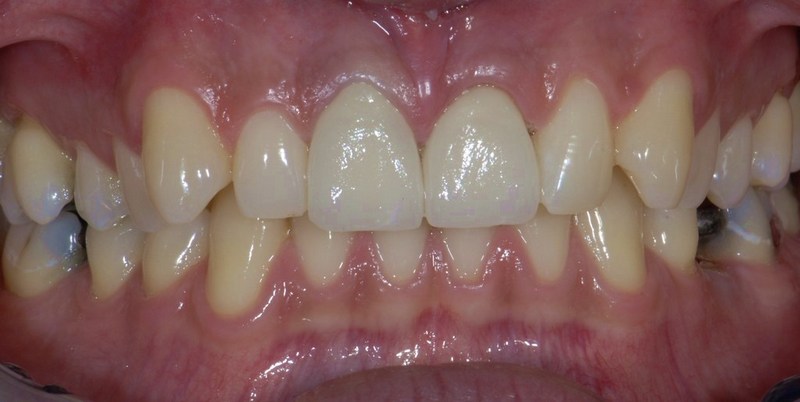

Dentalna protetika - krunice, mostovi, proteze

Vrhunska optička estetska i mehanička svojstva bezmetalnih keramičkih radova